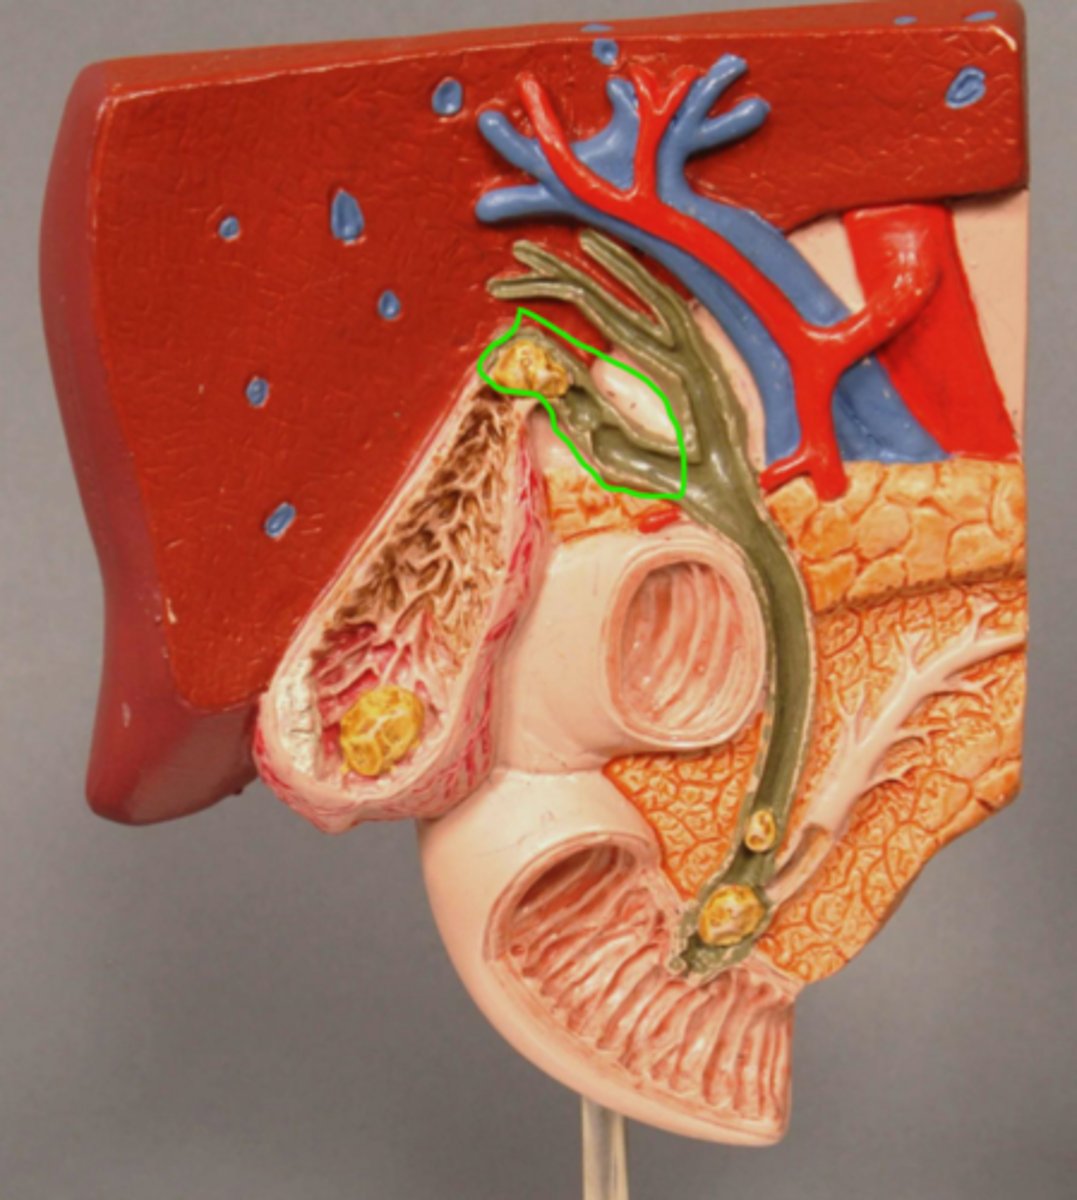

Cystic Duct

Gallstone at entrance to cystic duct

Left Hepatic Duct

Right Hepatic Duct

Common Hepatic Duct